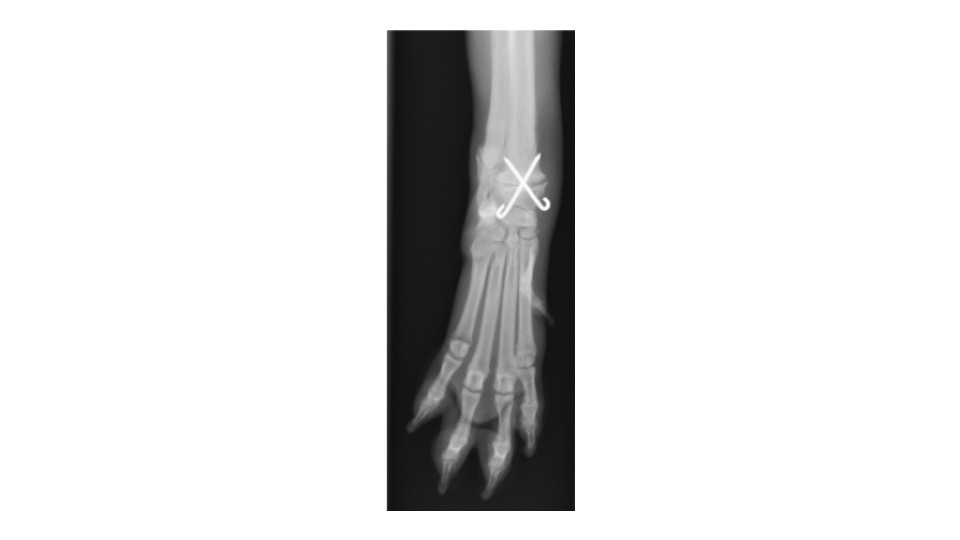

レントゲン検査を行ったところ、右手根骨のⅠ型成長板骨折が認められました。

→の部分が骨折部位になります。

この画像の曲線が、正常な成長板です。下の画像と比較してみると、わかりにくいですが骨折線が認められます。

成長板骨折は1方向だけのレントゲン画像では診断が難しいため、必ず2方向(横、正面)からの撮影を行います。

仔犬の成長板骨折は固く固定してしまうと、骨の成長を妨げてしまう為、ピンやスクリューを使った固定方法が一般的です。

骨折の型によって治療の方法は異なっており、今回はⅠ型の成長板骨折のため、2本のピンを使って手術を行いました。

手術を行って約1ヶ月半後に、2本のピンは抜去しました。